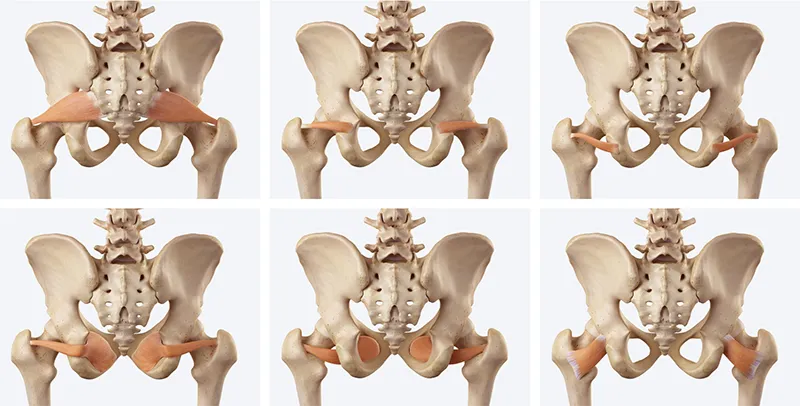

This imbalance between the gluteal muscles and the deep rotators represents the root dysfunction underlying many entrapment syndromes of the hip. The deep six lateral rotators (Image 2) are piriformis, superior gemellus, inferior gemellus, obturator internus, obturator externus, and quadratus femoris. Originating from the sacrum and ischium and inserting on or near the greater trochanter, they provide fine-tuned stabilization of the femoral head within the acetabulum and assist with lateral rotation during weight-bearing activities.